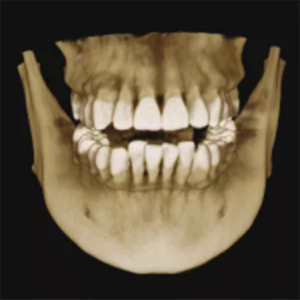

Furthermore, AI+PAN Dental CBCT Imaging enhances precision.

- The system rebuilds panoramic views directly from CBCT data using AI.

- Panoramic auto-focus and multi-layer technology select the best curve automatically.

- Therefore, the final image is cleaner and easier to read.